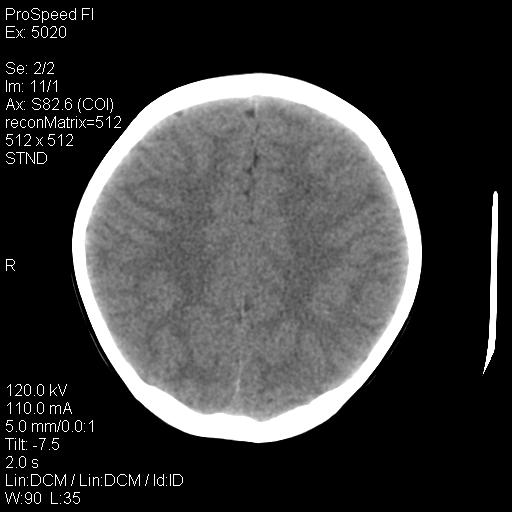

标题: PED1637:M 6Y 顶部无痛性包块两月。 [打印本页]

标题: PED1637:M 6Y 顶部无痛性包块两月。

2、颅骨局部缺失,边缘光滑、整齐

颅骨的病损表现为内外颅骨板层不规则的锋利的破坏,形成“斜边缘”,有一定的特点

颅骨为好发部位,生长缓慢,常位于顶骨、枕骨及颞骨,表现为颅骨缺损,呈圆形或椭圆形,边界清,无硬化

事发冠状缝与矢状缝交界区,密度较低,考虑表皮样囊肿可能性大,其次不除外嗜酸性肉芽肿